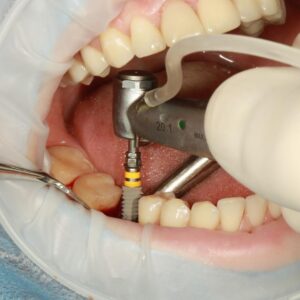

Concetto di trattamento All-on-4®

Lo studio Santarpia è considerato dalla ‘Nobel Biocare’ come l’eccellenza in questo tipo di chirurgia . Con il termine All-on-4®, che in italiano significa “tutto su 4”, si fa riferimento ad una tecnica di chirurgia implantare , che consente la riabilitazione di un’intera arcata dentale mediante l’inserimento di soli quattro impianti endossei. La metodica All-on-4®...